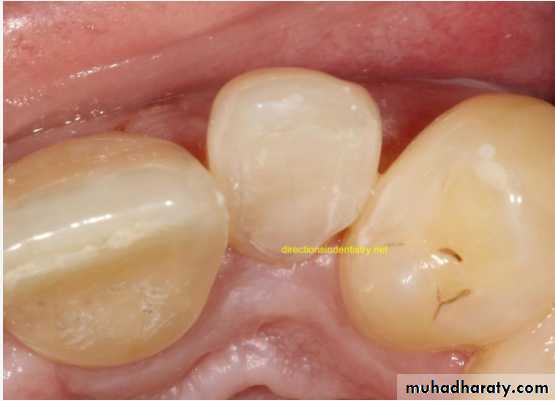

Gemination (twining):

*Gemination is a rare anomaly that arises when the tooth bud of a single tooth attempts to divide.

The result may be an invagination of the crown, with

partial division, or in rare cases complete division

throughout the crown and root, producing identical

structures. Complete twinning results in a normal tooth

plus a supernumerary tooth in the arch.

CAUSE: is unknown, or it may be familial.

*The patient has a larger tooth but a normal number of teeth overall, in contrast to fusion, where the patient would appear to be missing one tooth.

MANAGEMENT : Affected teeth can cause malocclusion and lead to periodontal disease.

the affected tooth may be removed (if it is deciduous).the crown(s) may be restored or reshaped.

OR the tooth may be left untreated and periodically examined to preclude the development of complications.

• Fusion of the left mandibular central and lateral incisors (twoindividual roots, two root canals and two joined crowns).

Gemination of right mandibular central incisor has one root, one root canal and a partially bifid dental crown.